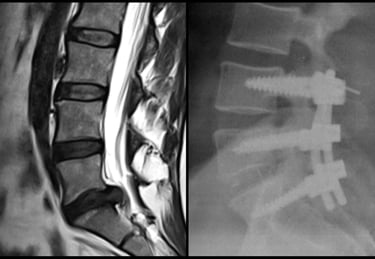

Artrodesis instrumentada, disectomia, cifoplastia, vertebroplastia, descompresion medular, liberacion radicular.

Cirugia columna vertebral